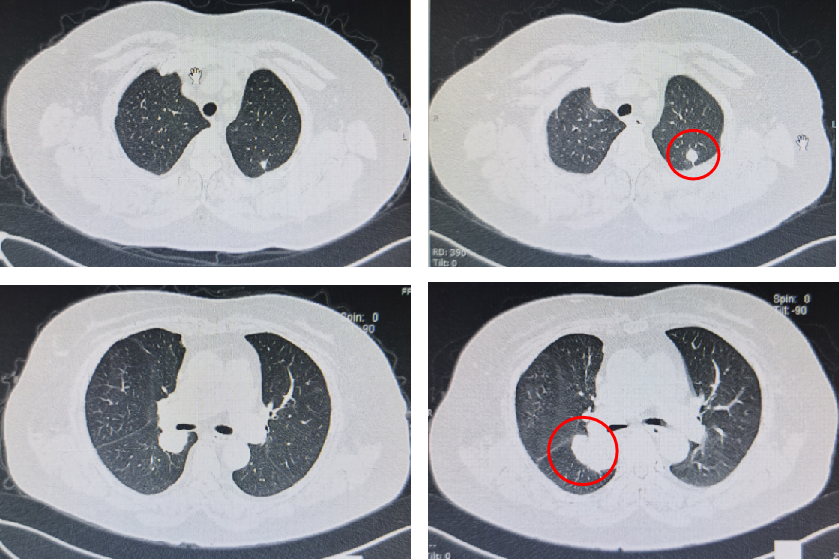

基本信息:性别 女,年龄 78岁,身高 159cm,体重 62kg。 主诉:结肠癌及肝转移瘤术后2年6个月(首次就诊时间为2018-09-10)。 既往史、个人史:“2型糖尿病”20年,予“二甲双胍 0.5g 口服 2次/日、门冬胰岛素注射液皮下注射,早 30U,晚 28U;甘精胰岛素皮下注射 20U ”降糖治疗,血糖控制一般。 家族史:无特殊。 02 初诊病史 体格检查、B超、CT及其他辅助检查。 体表面积1.60m,体格检查:浅表淋巴结未及肿大,双肺呼吸音粗,未闻及干湿性啰音,心律规整,未闻及杂音,腹壁可见陈旧性手术瘢痕,愈合良好,腹软,未及肿物,无压痛,肛查-,双下肢无水肿,起病隐匿,体检行腹部超声发现肝脏占位。 肠镜(2016-3-12):乙状结肠肿物。 咬检病理:(乙状结肠)腺癌。 肝胆胰增强CT(2016-3-10):肝左叶占位。 考虑:乙状结肠癌Ⅳ期 肝转移。 2016-3-21 于外院行“乙状结肠癌根治术+肝左叶转移瘤切除术”,术中予输血治疗,术后恢复慢,切口延期愈合。 术后病理:结肠中分化腺癌伴坏死形成,大者3.5cm×3.2cm×0.5cm,癌组织侵及浆膜脂肪层,脉管内癌栓形成,小者1cm×1cm×0.5cm,癌组织侵及粘膜下层。肠壁周围淋巴结癌转移(3/6),T3N1M1。(肝左叶)肝脏转移性腺癌伴大片坏死形成,大小6.6cm×6cm×4.5cm,结肠来源,残端及吻合口上下缘肠壁未见肿瘤侵及。 基因检测:KRAS、NRAS、BRAF 均未见突变。 初步诊断:乙状结肠癌Ⅳ期(pT3N1M1),同时性肝转移,中分化腺癌,2型糖尿病。 03 治疗方案 2016-4 XELOX 方案化疗1周期(具体剂量不详)因不良反应较重,未完成术后辅助治疗疗程。未予后续治疗,定期复查,病情稳定 胸腹CT(2017-3-19 ):右肺下叶新结节,考虑转移;肝左外叶转移瘤切除术后改变。 2017-4-1 于外院行局部肺肿物射频消融术,无治疗反应,恢复良好。 胸CT(2017-12-5):肺部新发结节,考虑转移。 【一线治疗方案(2017-12至2018-9)】 卡培他滨 1.5g po d1-14 q3w,共10个周期。 不良反应:1度消化道反应。 期间疗效评价:SD。 胸腹增强CT(2018-9-11):符合结肠癌切除术后,肝左叶切除后改变,双肺多发结节,部分较前增大。 2017-12-5 2018-9-11 建议调整方案治疗,患者家属拒绝,继续口服卡培他滨至2019年3月。 疗效评估: ECOG PS评分1分,新发活动后胸闷、气短症状 胸腹平扫CT(2019-3-26):双肺多发结节,较前增大;肝左外叶转移瘤切除术后改变。 2018-9-11 2019-3-26 评估PD。 【二线治疗方案(2019-4至2020-5)】 贝伐珠单抗 300mg ivgtt d0(体重62kg); 卡培他滨 1.5g po d1-14 q3w,共15周期。 不良反应:1级高血压、1度消化道反应。 疗效评估: 胸腹CT(2020-5-21):符合结肠癌术后、肝左叶切除术后,肝左切缘旁异常密度灶,左髂总动脉旁淋巴结;双肺多发结节,部分较前增大,右肺门肿物较前增大。 疗效评价:PD。 【三线治疗方案(2020-5至2020-10)】 西妥昔单抗 600mg ivgtt d0(体表面积1.66 m2); 亚叶酸钙 500mg ivgtt d1; 氟尿嘧啶 500mg ivgtt ,随后3500mg iv泵入 q2w,共9周期。 不良反应:无皮疹、腹泻、恶心、呕吐等。 疗效评估: 胸腹平扫CT(2020-09-07):右肺下叶背段软组织肿块,较前略减小,双肺多发小结节,转移瘤,同前;结肠癌术后、肝左叶切除术后改变,肝左切缘旁异常密度灶同前相仿,腹膜后左侧髂总动脉旁淋巴结同前。 2020-7-23 2020-9-7 疗效评价:SD(缩小趋势)。 胸腹平扫CT(2020-10-24):右肺下叶背段软组织肿块,较前(2020-9-7)略减小,双肺多发小结节,转移瘤,部分较前减小,结肠癌术后、肝左叶切除术后改变,肝左切缘旁异常密度灶同前相仿,腹膜后左侧髂总动脉旁淋巴结同前。 2020-9-7 2020-10-24 疗效评价:SD(缩小趋势)。 胸腹平扫CT(2020-12-13):右肺下叶背段软组织肿块,较前(2020-10-24)未见著变,双肺多发小结节,转移瘤,较前未见著变,结肠癌术后、肝左叶切除术后改变,肝左切缘旁异常密度灶同前相仿,腹膜后左侧髂总动脉旁淋巴结同前。 2020-12-13 疗效评价:SD。 患者未规律返院行西妥昔单抗维持治疗。 胸腹增强CT(2021-1-5):右肺下叶背段软组织肿块,较前(2020-12-13)增大,双肺多发小结节,转移瘤,左肺尖结节较前增大,余未见著变,左侧髂总动脉旁淋巴结较前增大。 疗效评价:PD。 【四线治疗方案(2021-1至2021-10)】 安罗替尼 8mg po 1次/日 d1-14 (2021-3 起因高血压2级,药物控制不佳调整为8mg qod ); 卡培他滨 1g po 2次/日 d1-14 q3w (2021-4 起因乏力2级不能耐受停服)。 不良反应:2级高血压,2级乏力,1级胆红素升高,1度消化道反应。 疗效评估: 胸腹增强CT(2021-10-3):右肺下叶背段占位,考虑恶性肿瘤,较前增大,双肺多发转移瘤,部分较前略增大,结肠癌术后、直肠区肠管明显扩张,肝左叶切除术后改变,切缘旁占位伴肝内胆管扩张,累及胆总管,考虑恶性病变,较前增大,腹膜后左侧髂总动脉旁淋巴结,较前增大,累及左侧输尿管伴以上输尿管及肾盂扩张。 2021-10-3 疗效评价:PD。 疗效评估: 胸腹增强CT(2021-10-3):右肺下叶背段占位,考虑恶性肿瘤,较前增大,双肺多发转移瘤,部分较前略增大,结肠癌术后、直肠区肠管明显扩张,肝左叶切除术后改变,切缘旁占位伴肝内胆管扩张,累及胆总管,考虑恶性病变,较前增大,腹膜后左侧髂总动脉旁淋巴结,较前增大,累及左侧输尿管伴以上输尿管及肾盂扩张。 【后线治疗方案(2021-10至2021-11)】 曲氟尿苷替匹嘧啶片(TAS-102) 40mg po 2次/日 d1-5,d8-12,q4w; 贝伐珠单抗 200mg ivgtt q2w。 不良反应:无皮疹、腹泻、恶心、呕吐等。 疗效评估: 胸腹增强CT(2021-11-17):右肺下叶背段占位,较前变化不明显,双肺多发转移瘤,较前变化不明显,结肠癌术后、直肠区肠管明显扩张,肝左叶切除术后改变,切缘旁占位伴肝内胆管扩张,累及胆总管,考虑恶性病变,较前变化不明显,腹膜后左侧髂总动脉旁淋巴结,较前减小,肾盂扩张较前减轻。 疗效评价:SD。 胸腹增强CT(2021-11-17):右肺下叶背段占位,较前变化不明显,双肺多发转移瘤,较前变化不明显,结肠癌术后、直肠区肠管明显扩张,肝左叶切除术后改变,切缘旁占位伴肝内胆管扩张,累及胆总管,考虑恶性病变,较前变化不明显,腹膜后左侧髂总动脉旁淋巴结,较前减小,肾盂扩张较前减轻。 04 病例小结 患者为高龄女性,诊断为直肠癌Ⅳ期多发转移,KRAS、NRAS、BRAF 均未见突变。 OS为69个月。